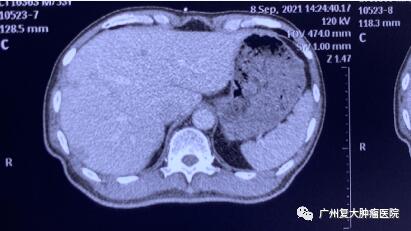

图2

为减轻肿瘤负荷,改善生活质量,延长患者生命,经患者及家属同意,我院牛立志院长为其实行胰腺肿瘤、肝脏肿瘤不可逆电穿孔治疗,术中以胰腺肿瘤、肝脏10个病灶为靶区消融。术后联合化疗加免疫药物治疗进一步改善治疗效果。

术后一周检查发现,身体各项指标逐步恢复正常。与之前相比,上腹部MRI图像提示胰腺、肝脏肿瘤中心大部分坏死。术后一年复查显示,肿瘤缩小,得到较好的控制。